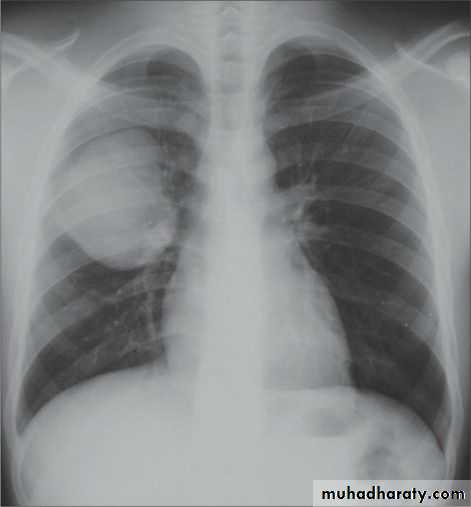

Severe dyspnea with shock